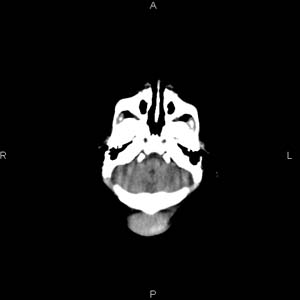

患者男,27天,出生后正常,今天中午在母亲怀里抱着吃奶在放下睡觉时发现后枕部慢慢出现一包块,来查头颅ct。无外伤史。包块内ct值47-51hu。请大家讨论。

碰着了吗,感觉枕骨有点凹陷似的,头皮血肿吧要是碰着的话

头皮下血肿,局部枕骨略有凹陷

枕部皮下血肿 局部枕骨凹陷

颅骨无缺损,骨缝无增宽.支持头皮血肿(血管破裂)